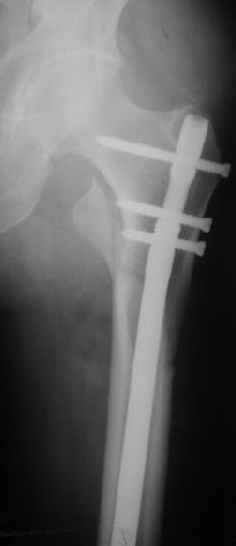

Картинка красивая, но на мой взгляд, не совсем оптимальная: Слишком медиально введён стержень - риск аваскулярного некроза головки бедра.

вариант межфрагментарного шинирования - зона достаточно простительная т.е. чрезвертельные переломы потенциально хорошо срастаются при любом

расположении сопредельных отломков- хорошая локальная васкуляризация. В приведённом случае я бы предпочёл принцип межфрагментарной компрессии (рекон/гамма нэйл 130- 135) принципу шинирования перелома.

Поясни, пожалуйста, почему решил шинировать косой чрезвертельный перелом?

Женя, эта картинка показывает не оптимальное лечение вертельных переломов в моем представлении, а особенности дизайна упомяутого фиксатора.

В частности, его возможности при фиксации переломов проксимального отдела бедра - в сравнении с другими, имеюшими лишь по одному статическому и динамическому отверстию и с кондуктором для введения 2 винтов.

Это было года 2,5 назад, мы тогда еще уточняли возможности шинирования с угловой стабильностью гвоздем с поперечным расположением винтов при переломах проксимального отдела бедра. Пациенту не пришлось приобретать намного более дорогой рекон или проксимальный гвоздь. В приложении еще несколько примеров применения того гвоздя при высоких переломах бедра, в том числе с более латеральной точкой входа. Гвоздь изгибаем для этого.